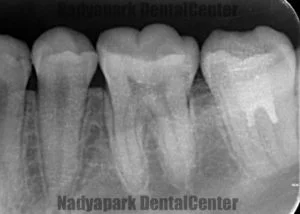

深い虫歯でも神経を抜かずに保存する「バイタルパルプセラピー」の事例

治療1回 + 経過観察2~3回 / 50,000円(税別)リスク・副作用:処置後、一時的に痛みやしみる症状が出ることがあります。神経の状態によっては、後に神経をすべて抜く処置が必要になる可能性があります。